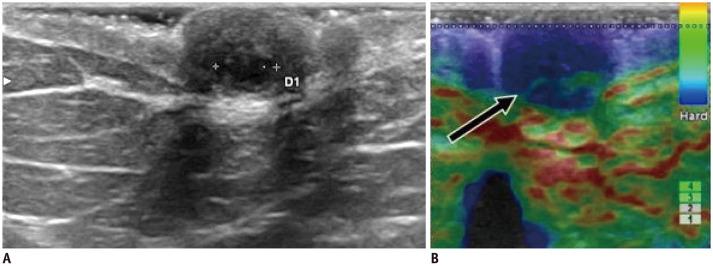

Ultrasound (US) is an attractive diagnostic approach to identify both common and uncommon nipple pathologies, such as duct ectasia, nipple abscess, nipple leiomyoma, nipple adenoma, fibroepithelial polyp, ductal carcinoma (restricted to nipple), invasive carcinoma, and Paget's disease. US is the reliable first-line imaging technique to assess nipple pathologies. It is useful to identify and characterize nipple lesions. Additionally, we have presented the mammography and MRI outcomes correlated with histopathologic features for the relevant cases.